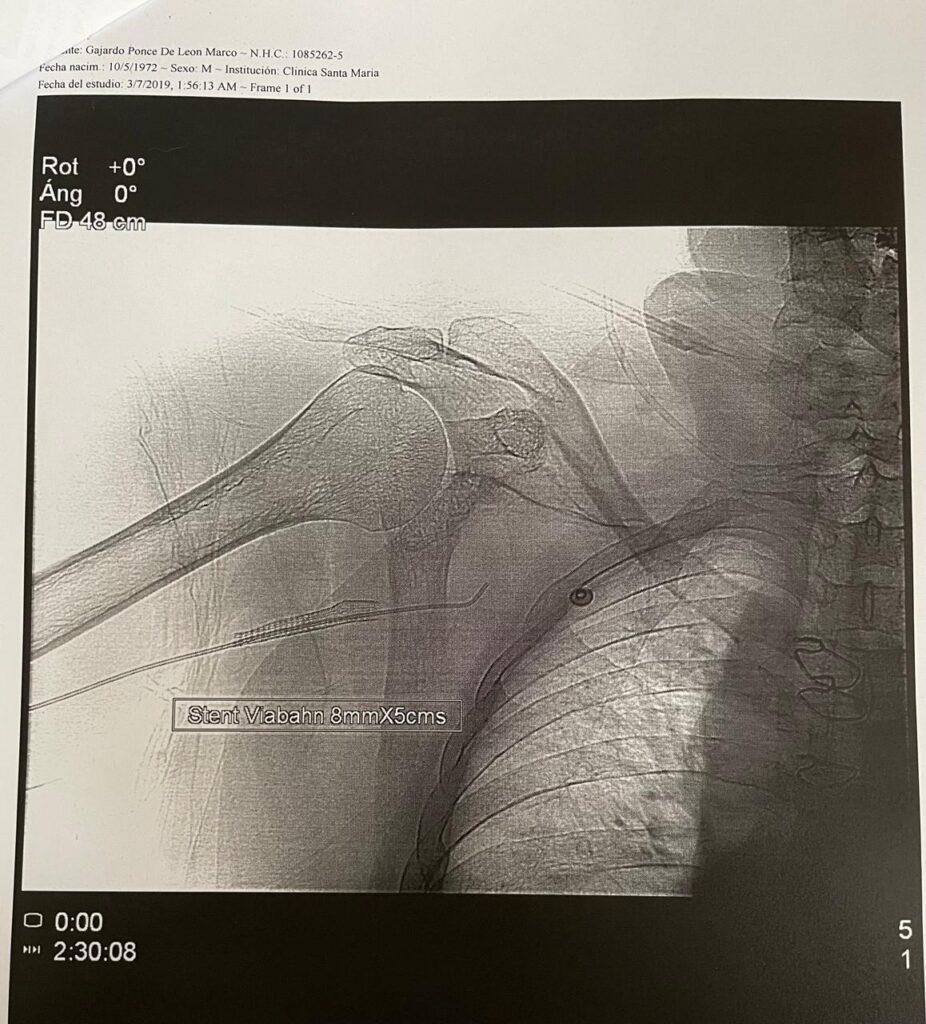

| 2 Stents (2019) |

Stents